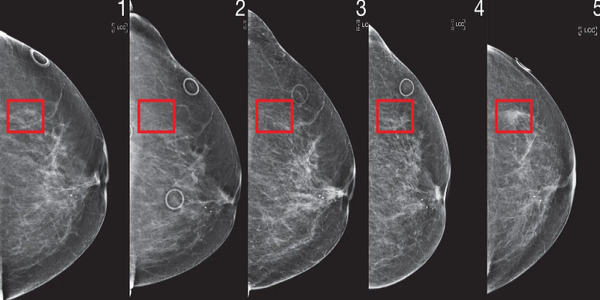

Алгоритамот ги анализирал и претходните мамограми и се чини дека функционира дури и кога лекарите не ги гледаат знаците на предупредување во претходните скенирања.

Фото: MIT

Алгоритамот ги анализира стандардните четири прегледи со мамограф, од кои потоа донесува заклучоци за пациентот, како историја на операции или хормонски фактори, како што е менопаузата. Ова може да помогне ако тие податоци претходно не се знаеле.

Откриено е дека „Мираи“ е попрецизен од статистичките модели кои обично се користат за проценување на ризикот од рак на дојка кај жените. Јала вели дека моделот генерализира добро поради големата, доволно разновидна база на податоци што ја користи, но забележува дека секогаш е важно да се потврдат алгоритмите во различни поставки.